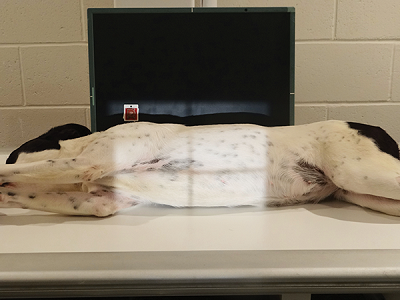

ventrodorsal projection of abdomen with the horizontal beam (lateral decubitus)